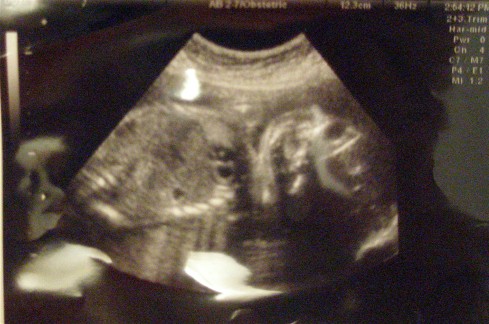

As for the baby, she couldn't be more perfect. My OB said she was measuring perfectly and her heartbeat is strong. Physically, this has been a rather uneventful pregnancy and I am very grateful.

I'll post pictures later but they make Ed-lie look like a lizard.

PICS of the lizard:

oh you have my lizard baby!!

my little is always sleeping face down like that... so cute

Seriously, her nose was so much cuter the last time. Im going to say she wasn't as cooperative this time and maybe when I go for my GTT next week, I can sneak in another sono and figure out if I need to start saving for college or rhinoplasty.